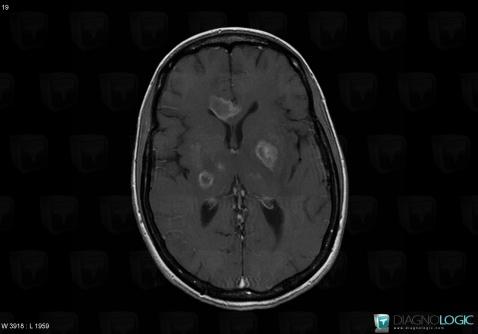

Toxoplasmosis, Cerebral hemispheres, MRI

Here is the specific information in the key image above:

- Diagnosis Toxoplasmosis (link to Abscess), Location(s) Cerebral hemispheres, with gamuts Intracerebral lesion with intense enhancement